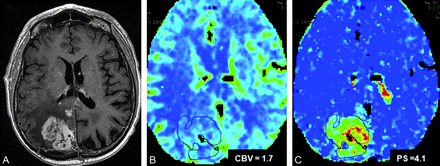

A 77-year-old man with an initial diagnosis of glioblastoma multiforme who underwent GTR, chemotherapy, and RT (EBRT, 60 Gy). A, Follow-up MR image shows a recurrent enhancing lesion 26 months post-RT in the right parieto-occipital region within the radiation field. B and C, CBV (B) and PS (C) maps show high rCBV and PS, suggesting RPT, which was confirmed with histopathology.